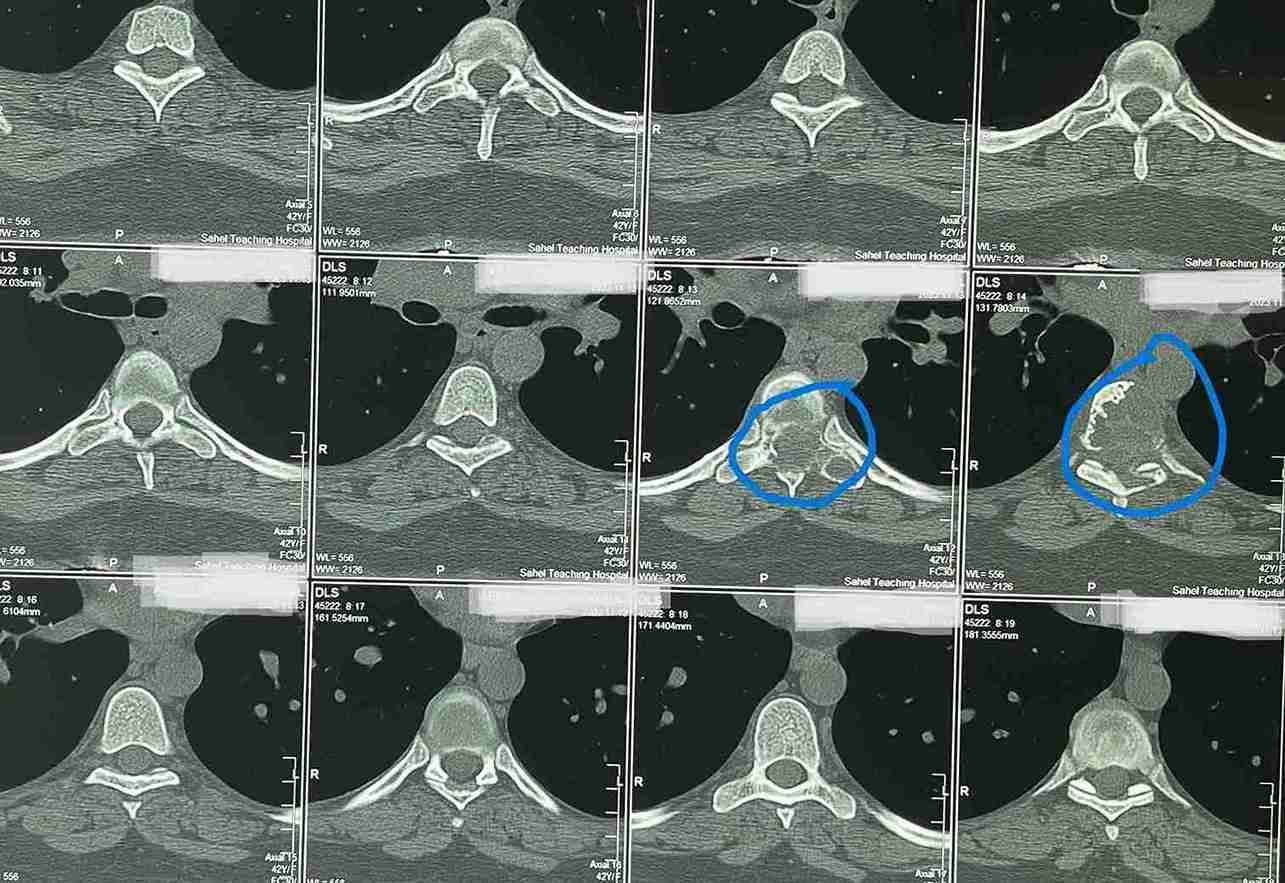

بعد عمل الاشعات تبين وجود ورم التكيس الدموي المتمدد بالفقرة الصدرية السادسة.

وذلك موضح بصور الاشعات قبل وبعد الجراحة . وقد تحسنت المريضة واستعادت كامل الوظايف العصبيىة واصبحت تمارس حياتها بصورة طبيعية.